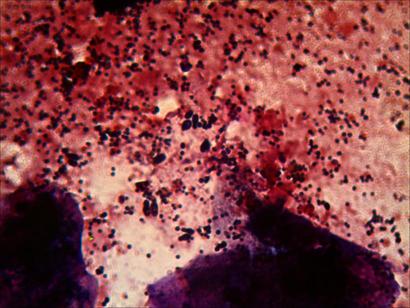

Ahora vamos a las fotos……las manchas grandes de tonos rosados y violaceos, son escamas,restos de piel en las que a veces se observan algunas celulas deterioradas bastante bien…..en la primera foto vemos, los puntos negros son cocos, que estan haciendo las clasicas agrupaciones en racimo de los estafilococos…..en la parte central izquierda, podemos ver un grupo de levaduras de malassezia((hongos))….estas se distinguen de las bacterias, principalmente por su forma ahuevada y su tamaño superior, y en algunos casos las vemos en proceso de gemacion((reproduciendose)).

La segunda foto, son básicamente levaduras, tanto la mancha oscura y poco clara de la parte superior como la de la paret inferior.

En la tercera vemos un popurri mucha bacteria y algunas levaduras, y la cuarta son todo levaduras.